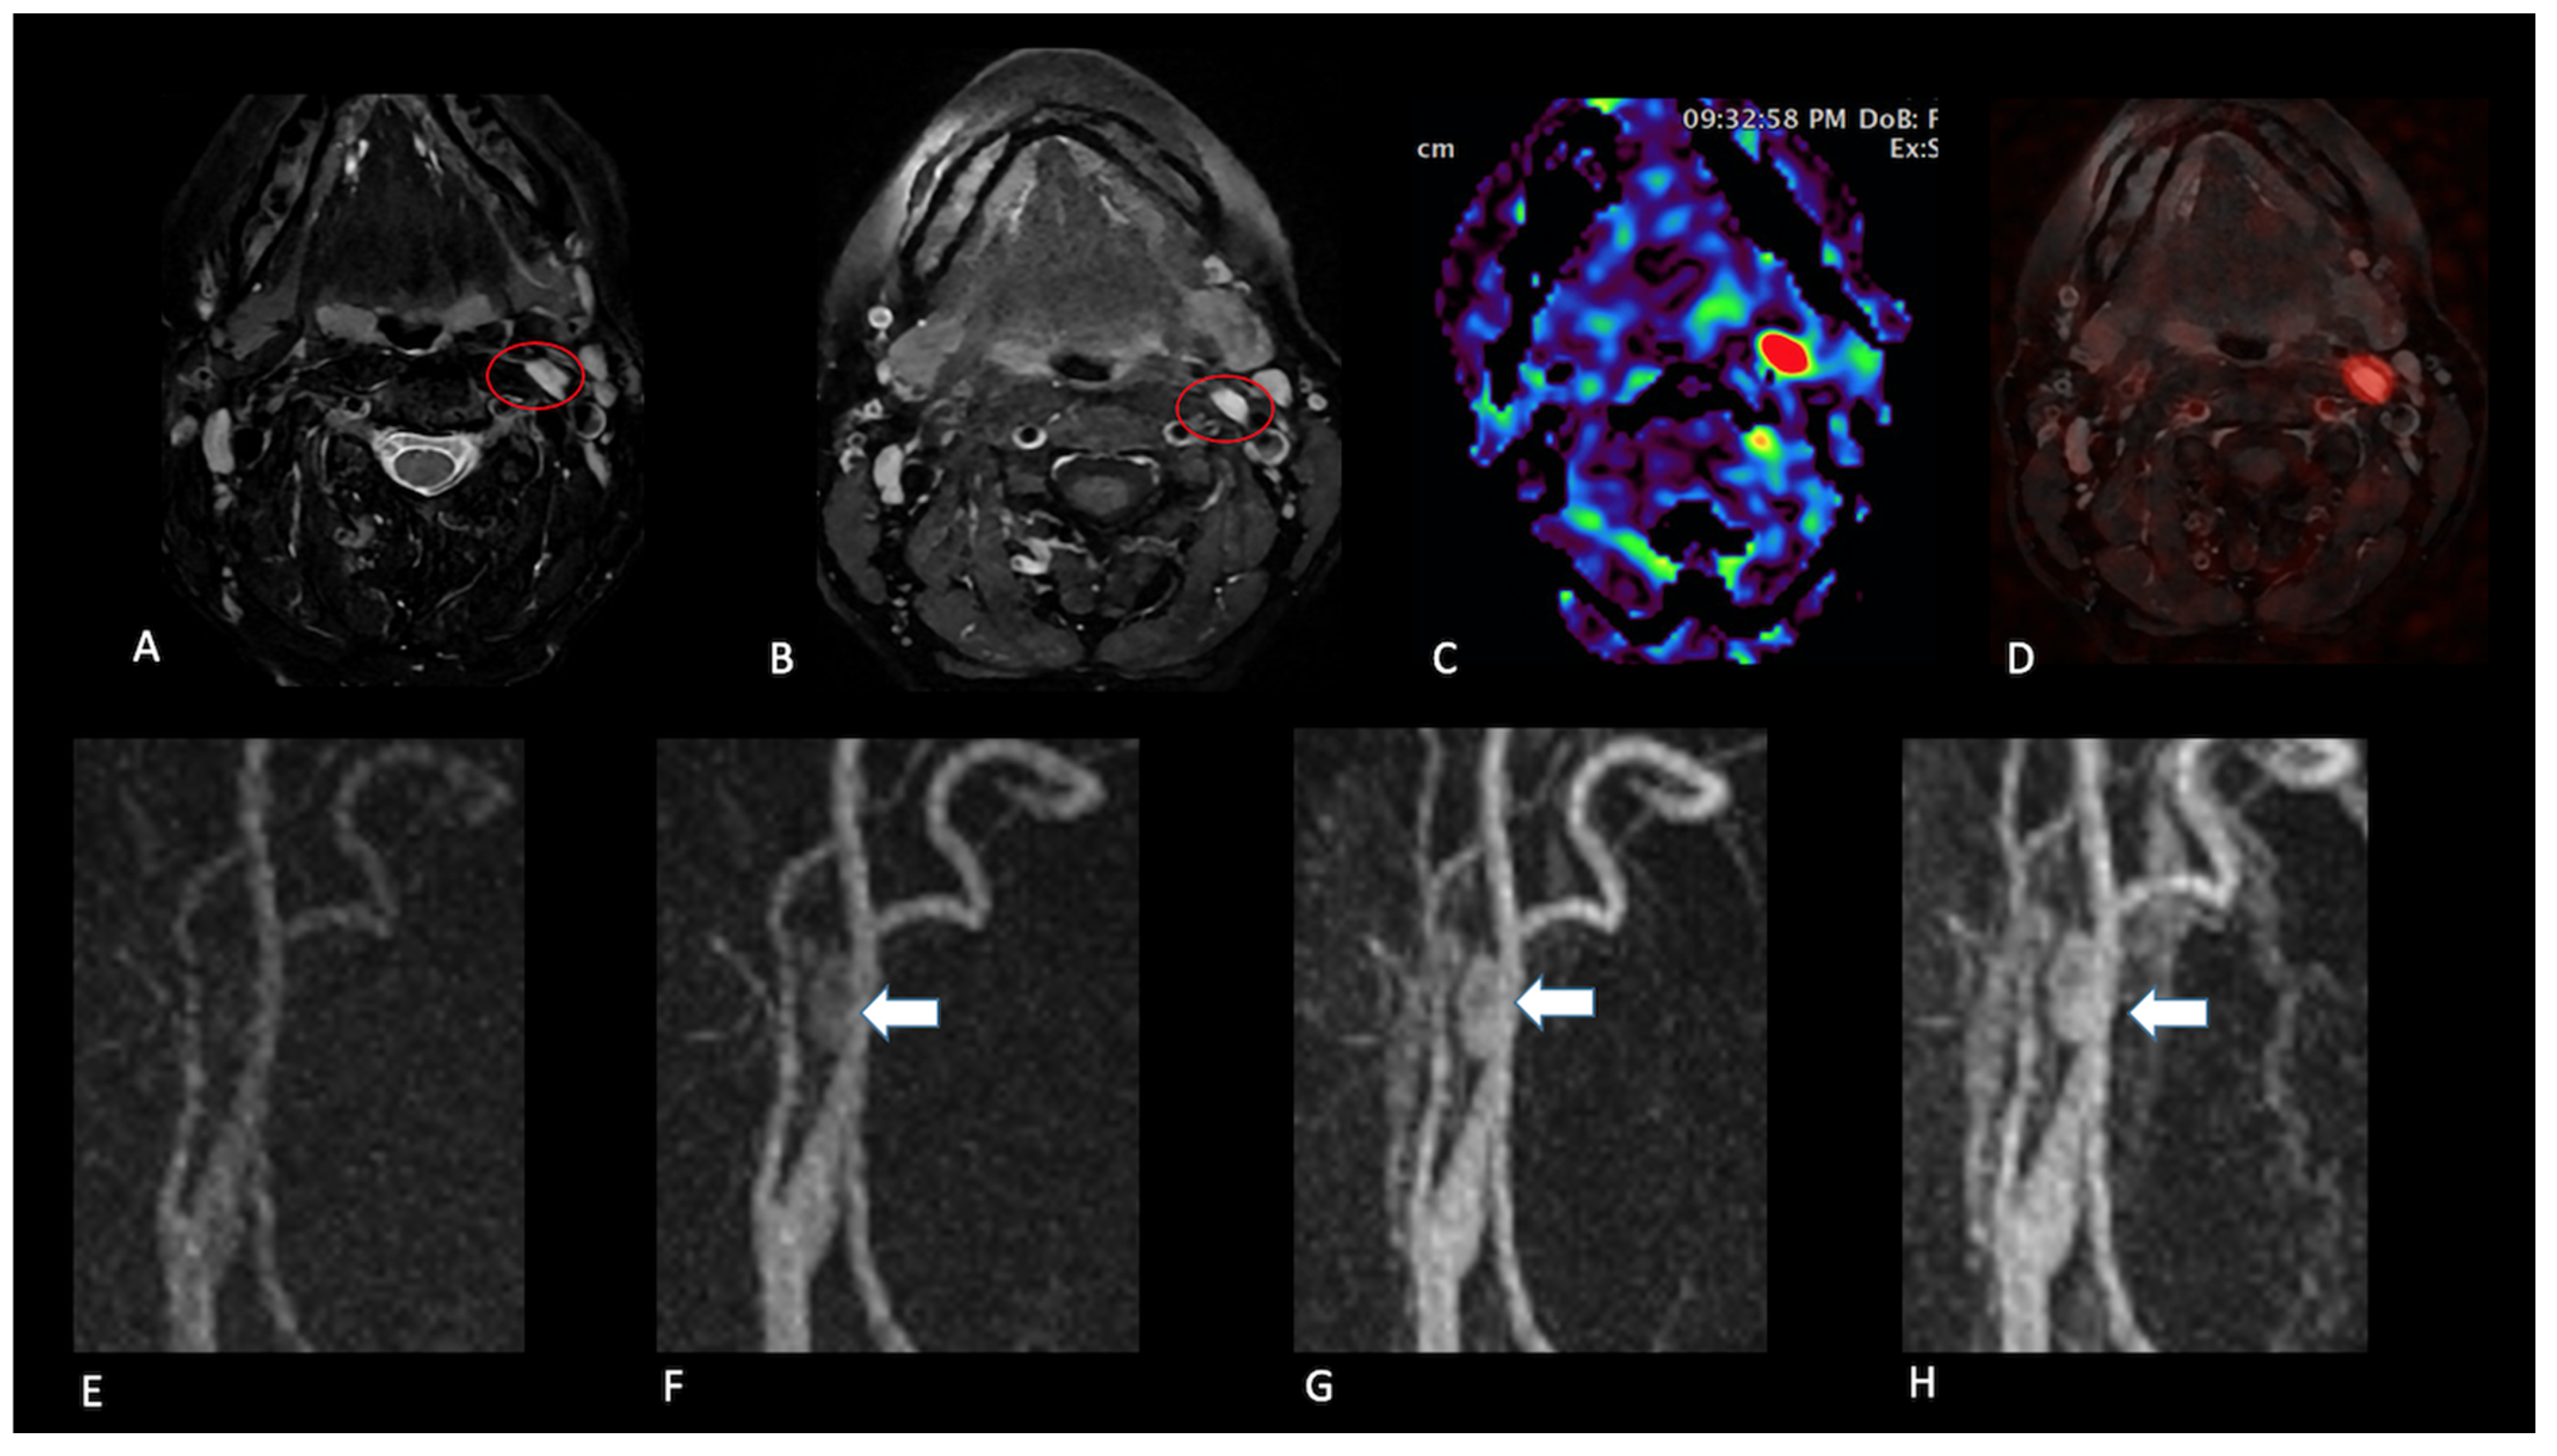

- Presence (present | indeterminate | absent) and site of a lesion.

- Sequence(s) providing greatest diagnostic confidence in detecting/localising NPGLs:

- Single sequences—FS-T2, CE-FS-T1, pcASL, and TRICKS;

- Combined sequences—FS-T2 + CE-FS-T1, and pcASL + TRICKS.